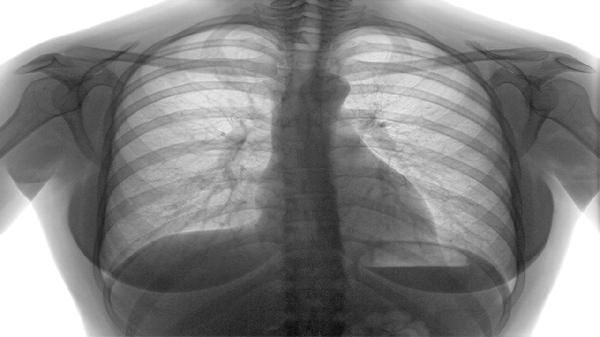

慢性阻塞性肺疾病的核心病理改变是气道壁增厚、黏液分泌增多以及肺泡结构破坏,导致呼气时气道塌陷。患者常出现活动后气短,随着病情进展,静息状态下也会感到呼吸困难。典型肺功能检查显示第一秒用力呼气容积与用力肺活量比值降低,这种气流受限呈不完全可逆性。